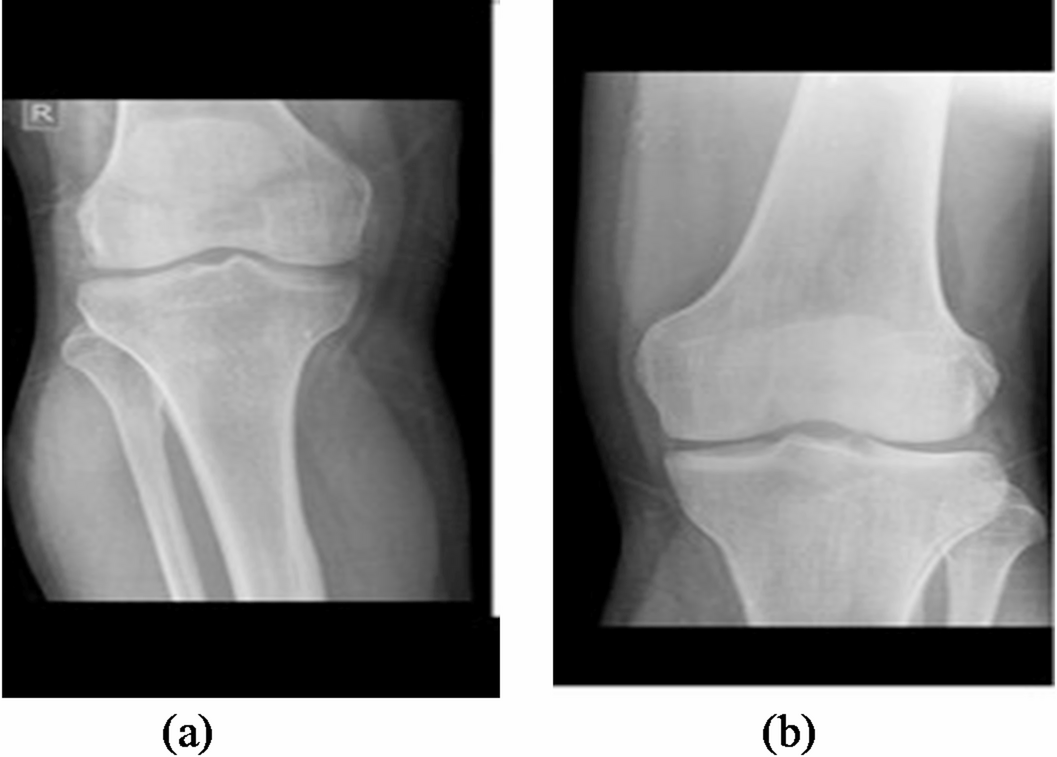

Normal knee x-ray.